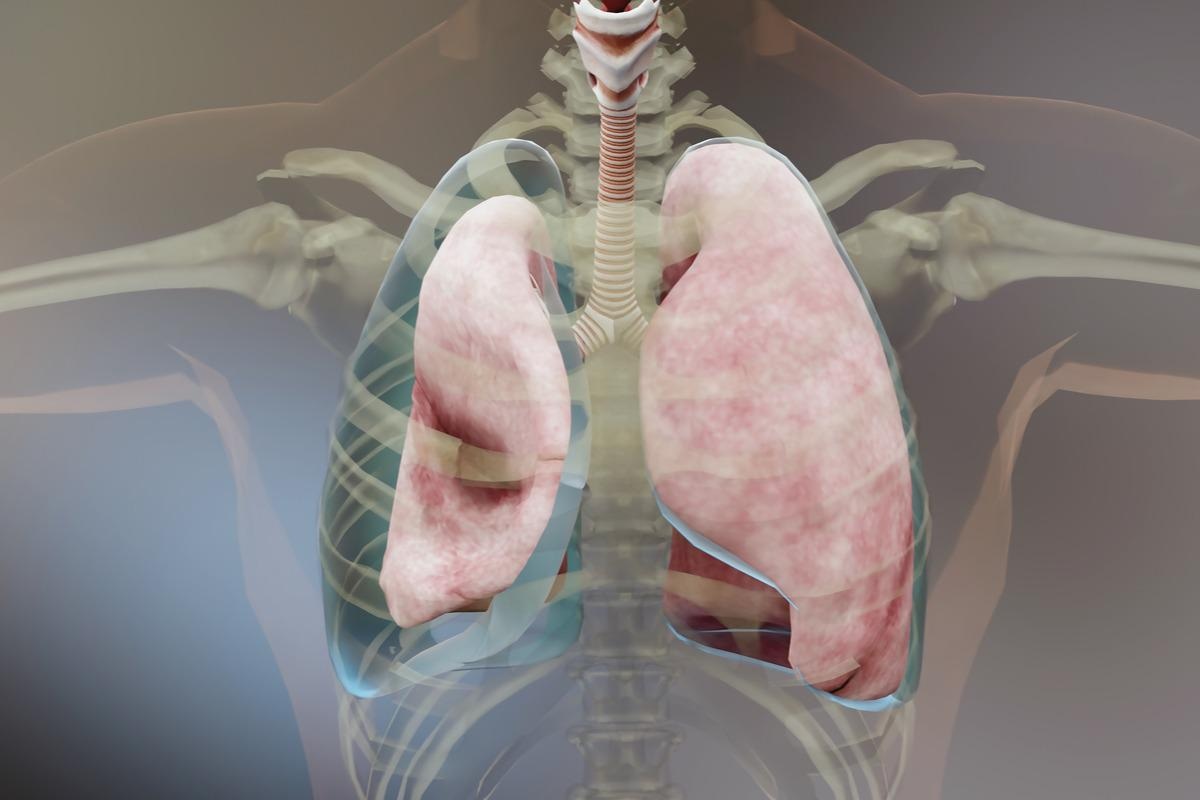

A pleura is a smooth layer that covers the interiors of the chest cavity and lungs. A thin space known as pleural space is filled with pleural fluid that separates these layers, which are almost in contact. This fluid sometimes accumulates and becomes infectious, and the collection of pus begins, which thickens and leads to the sticking of the pleural layers, forming pus pockets. As the accumulation of the fluid increases, the pus pockets increase, and the thick fluid begins coating the outer layer of the lungs blocking them from expanding and worsening the empyema.

The progression of empyema can be characterized by a series of events. The exudate stage is characterized by an increase in fluid production in the pleural cavity during an inflammatory process such as pneumonia. Microorganisms, most often bacteria, start colonizing the fluid and cause empyema as the disease progresses. This fluid contains higher levels of neutrophils, proteins, lactate dehydrogenase, and dead cells. The fibrinopurulent stage is characterized by a thick opaque fluid. Following the resolution of the infection, as a result of the inflammation, a fibrotic process occurs that can lead to the limitation of the lung parenchyma.

Image Credit: Good Image Studio/Shutterstock